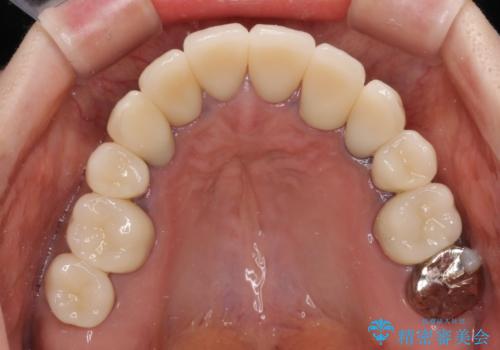

- 近医にて古いかぶせ物をセラミッククラウンにしようと治療を開始したものの、仮歯での咬み合わせが不安定とのことで、転院を希望して来院された患者様です。

骨格的に下顎骨が前方位に位置しており、上下前歯部の先端同士が接触する切端咬合でした。

このような方は咬み合わせが大きく変わると不安定となるため、まずは装着されている仮歯で咬合調整を行い、安定した咬み合わせとした後に、新しい仮歯に置き換え、その後オールセラミッククラウンにて補綴治療を行うこととしました。

仮歯で咬み合わせの調整を行ってからは、特に不安定になることもなく、非常にスムーズに治療を進めて行くことができました。

前歯奥歯ともに望ましくない力がかかりやすい咬み合わせであるため、就寝時にはマウスピースを使用するようにお伝えしております。